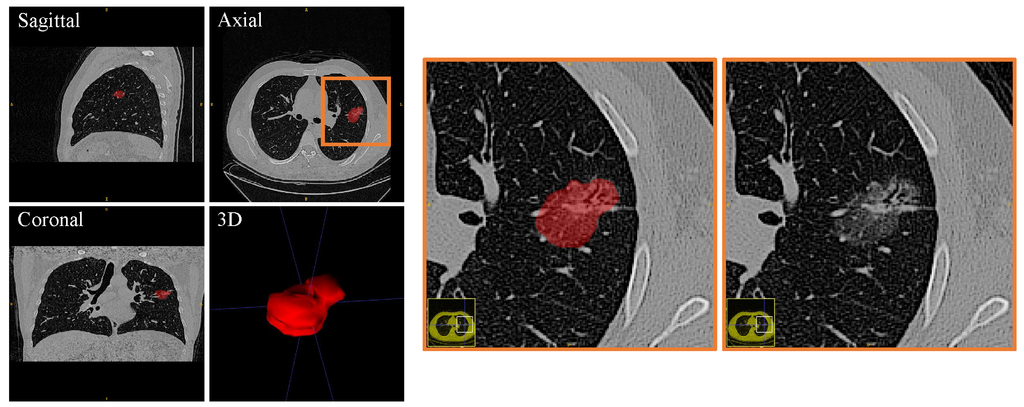

Background

Adenocarcinoma (ADC) is the most common histological subtype of lung cancers in non small cell lung cancer (NSCLC) in which ground glass opacifications (GGOs) found on computed tomography (CT) scans are the most common lesions. These lesions are usually treated with limited lung resection. However, the presence of a micropapillary or solid component is identified as an independent predictor of prognosis, indicating a more extensive resection. The accurate classification of subtypes still remains difficult in radiology or in frozen pathological analysis, even with the help of classical radiomics. The purpose of our study is to explore imaging phenotyping using a novel method combining radiomics with deep learning (RDL) to predict high-grade patterns within lung ADC.

Included in this study were 111 patients differentiated as having GGOs and pathologically confirmed ADC. Four different methods were compared to classify the GGOs for the prediction of the pathological subtypes of high-grade lung ADCs, including classic machine learning, radiomics, deep learning method, and a proposed novel method referred as RDL. A four-fold cross-validation approach was used to evaluate the performance of such methods.

We analyzed 32 patients with high-grade patterns and 79 without such patterns. The proposed RDL has achieved an overall accuracy of 0.888, which significantly outperforms classic machine learning, radiomics, and deep learning alone (p< 0.001, paired t-test).

High-grade lung ADC based on histologic pattern spectrum in GGO lesions might be predicted by a novel framework combining radiomics with deep learning, which reveals a significant advantage over traditional methods.